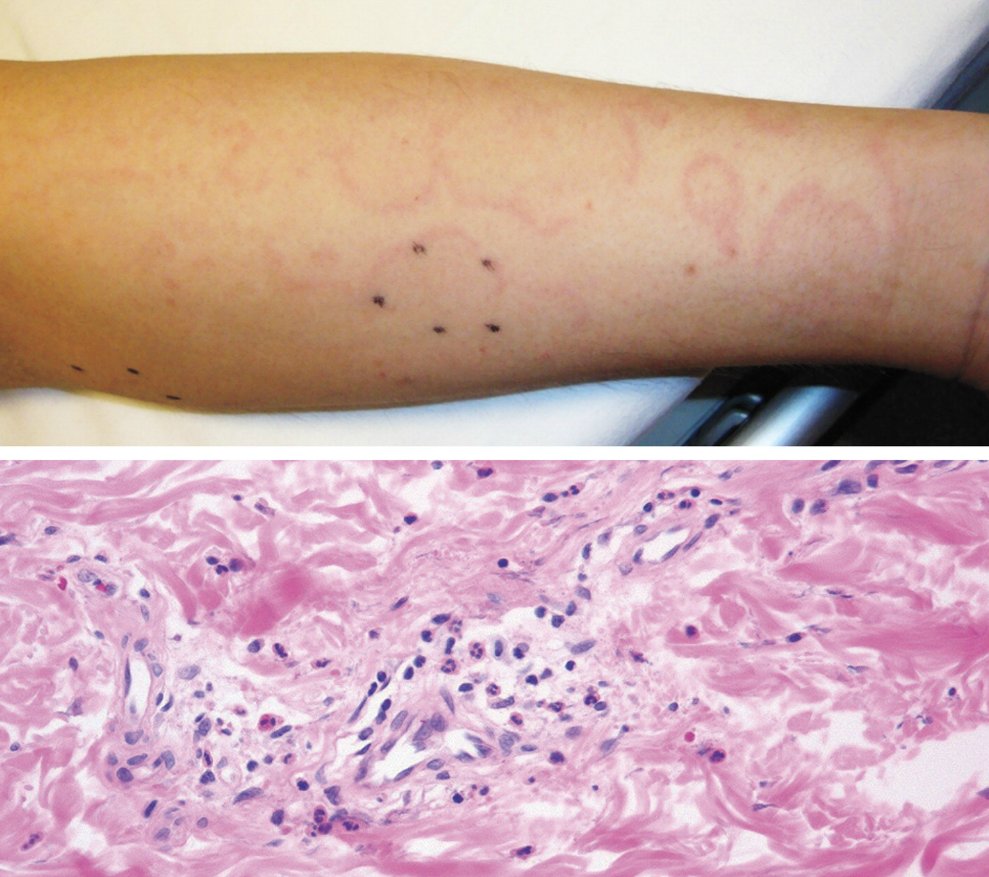

Images in Clinical Medicine: Acute Rheumatic Fever with Erythema Marginatum http://nej.md/2hSAaPm pic.twitter.com/6oHwysq2wB